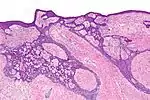

| Type | Histopathology | Other characteristics | Image |

| Cystic basal-cell carcinoma | Morphologically characterized by dome-shaped, blue-gray cystic nodules.[27]: 647 | ![]() | |

| Morpheaform basal-cell carcinoma (also known as "cicatricial basal-cell carcinoma", and "morphoeic basal-cell carcinoma") | Narrow strands and nests of basaloid cells, surrounded by dense sclerotic stroma.[29] | Aggressive[26]: 748 [27]: 647 | ![]() |

| Infiltrative basal-cell carcinoma | Deep infiltration.[27]: 647 | Aggressive[27]: 647 | |

| Micronodular basal-cell carcinoma | Small and closely spaced nests. | ![]() | |

| Superficial basal-cell carcinoma (also known as "superficial multicentric basal-cell carcinoma") | Occurs most commonly on the trunk and appears as an erythematous patch.[26]: 748 [27]: 647 | ![]() | |